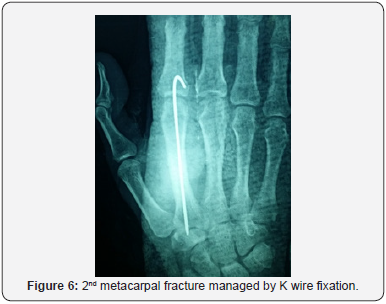

Postoperatively, a well-molded short arm slap, ulnar gutter or radial gutter in the intrinsic-plus position was applied for all the patients. Patients were encouraged to start full finger motion active and passive exercises within the splint the following day. Five weeks after surgery or when there were radiographic signs of bone healing, the wires were removed and patients were encouraged to perform wrist and finger motion exercises more vigorously without a splint (Figures 5 & 6).